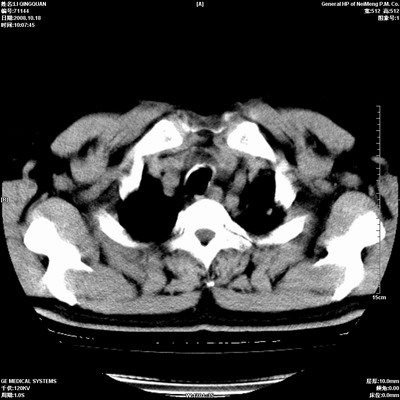

以下是引用duguo在2008-10-19 13:59:00的发言:[br]左肺上叶支气管狭窄,首先考虑中心型肺癌伴阻塞性肺炎\\肺不张.

以下是引用ybing在2008-10-19 12:58:00的发言:[br]左肺上叶阻塞性炎症-建议支气管镜进一步检查除外中央型肺癌

以下是引用随光逐影在2008-10-19 14:31:00的发言:[br]考虑左肺中央型肺癌并左肺上叶阻塞性肺炎,肺不张。